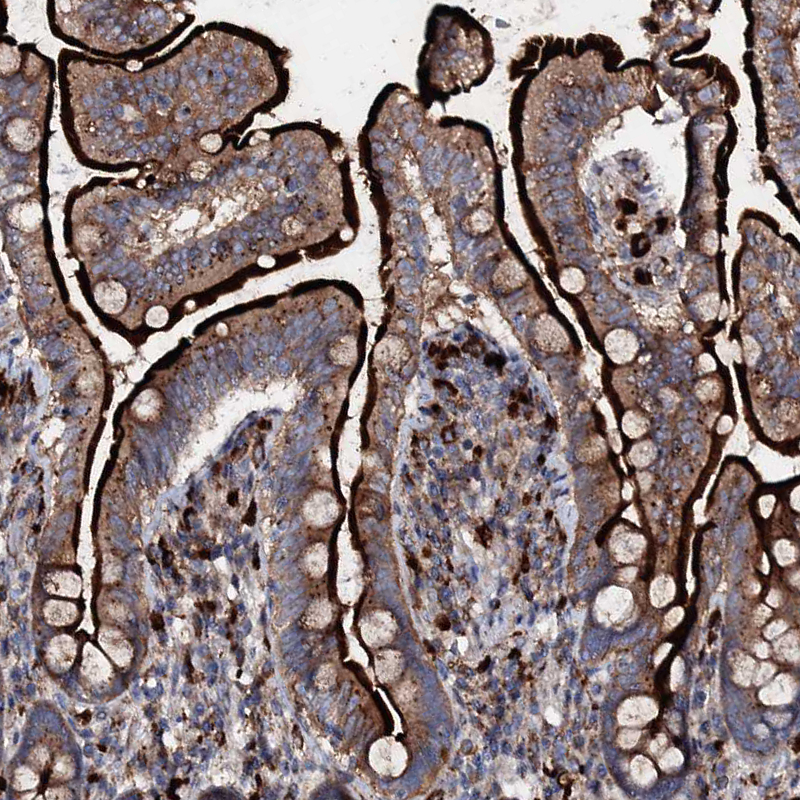

Immunohistochemistry analysis in human placenta and skeletal muscle tissues using HPA039494 antibody. Corresponding P2RX4 RNA-seq data are presented for the same tissues.